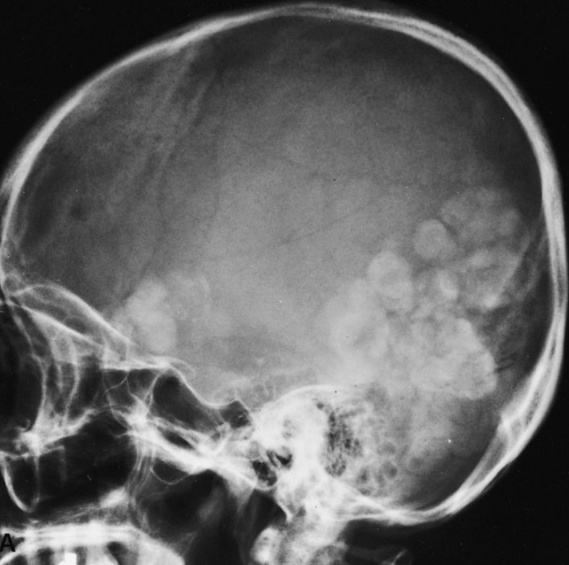

Hilar calcifications: on Xray

farmer on left. Cactus: fungus balls. Aspergillomas form in cavities, such as in TB/klebsiella cavities. People with cavities in lungs already are at risk

peanuts underground: Aspergillomas are gravity-dependent, fungus at bottom of cavity on chest xray